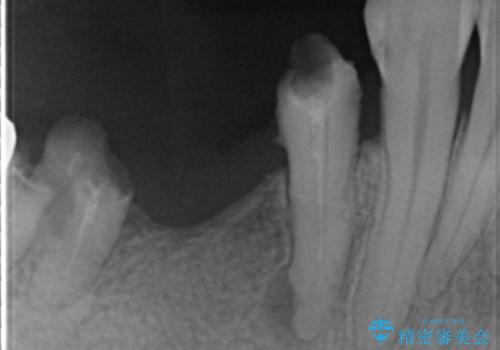

精査したところ、右下4の根尖病変及び右下5の欠損を認め、右下6は残根となり保存不可能な状態でした。

保存不可能な歯を抜去後、インプラント治療と根管治療を行いました。